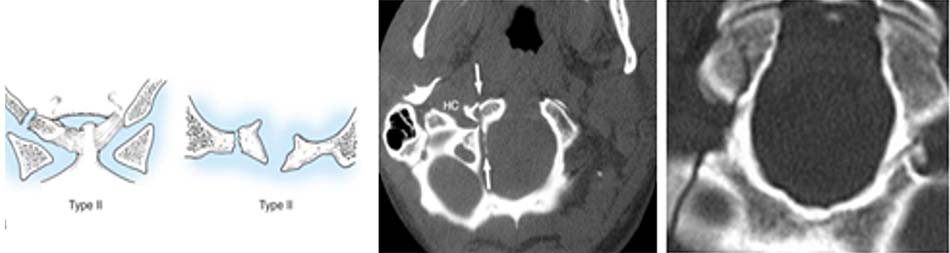

Vị trí thương tổn thường ở 4 điểm yếu ở cung trước và cung sau, nơi tiếp giáp với 2 khối bên. Có nhiều cách phân loại thương tổn, Levine và Edwards [20] phân thành 3 loại thương tổn theo vị trí và số điểm gãy trên cung trước, cung sau:

- Loại I: vỡ cung sau C1 đơn thuần, tổn thương thường gặp nhất, gãy vững, không tổn thương dây chằng ngang.

Hình 1.24. Hình ảnh vỡ cung sau C1 đơn thuần (loại 1) - Loại II: gãy kết hợp một cung trước và một cung sau do lực ép thẳng trục phối hợp với nghiêng đầu. Thương tổn ít gặp nhất của vỡ C1. Hậu quả làm bửa một khối bên C1.

Hình 1.25. Hình ảnh vỡ cung sau C1 (loại 2) - Loại III: vỡ vụn C1 (gãy Jefferson). Tổn thương thường gặp sau gãy loại I, cơ chế do lực nén thẳng trục với tư thế đầu trung gian, tổn thương gãy 2 điểm cung trước và 1 hoặc 2 điểm ở cung sau.

Hình 1.26. Hình ảnh vỡ vụn C1 – gãy Jefferson (loại 3)